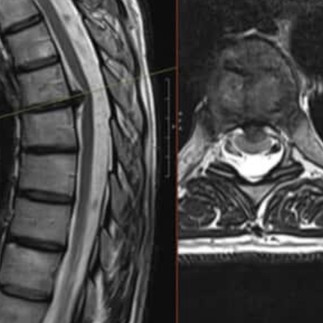

ACD VS PECF

which surgery would you offer?